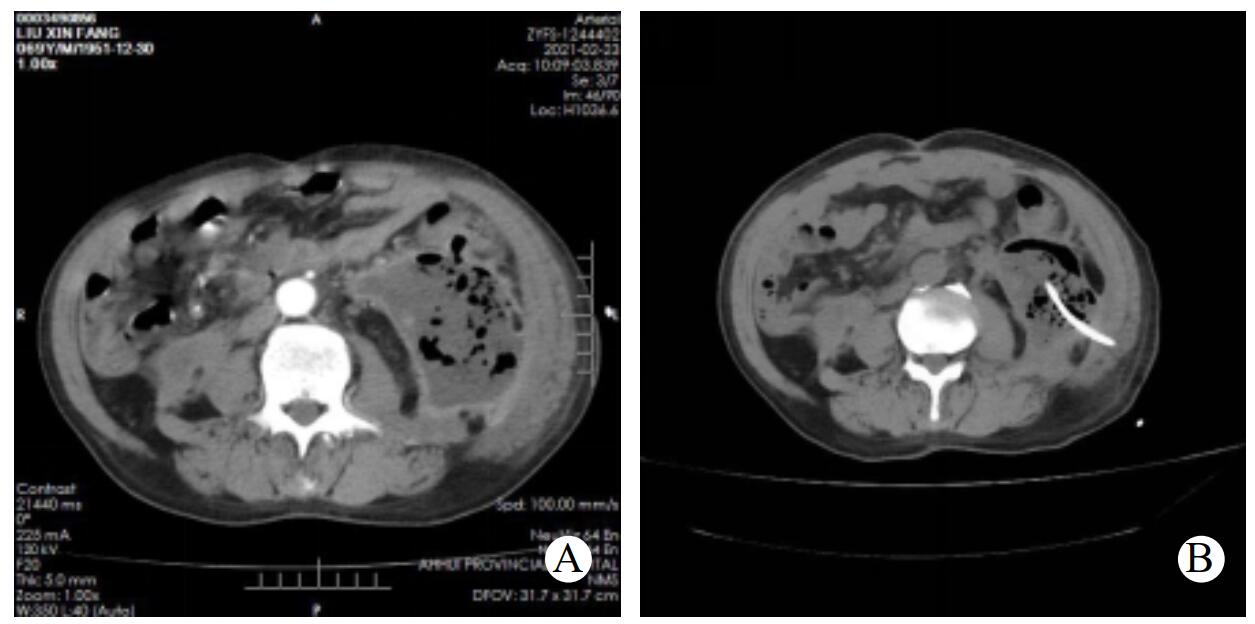

1.2 研究方法步骤一,经皮穿刺置管引流(pereutaneous catheter drainage, PCD):诊断明确的感染性胰腺坏死的患者,局部麻醉,在CT引导下选择合适的穿刺路径,尽量避开肝脾等实质脏器及胃肠道等消化道,采用Seldinger法穿刺置入14 F或16 F管径的猪尾巴引流导管,见图 1。置管成功后即可抽取脓腔内的液体留作细菌培养及药敏试验,后每日经引流导管给予生理盐水间断冲洗两次,一般以冲洗液无明显脓性液体或沉渣为标准。

| A:CT增强CT提示左侧腹膜后感染性胰腺坏死;B:CT引导下PCD置入猪尾巴导管 图 1 行PCD治疗前及PCD后CT表现 |